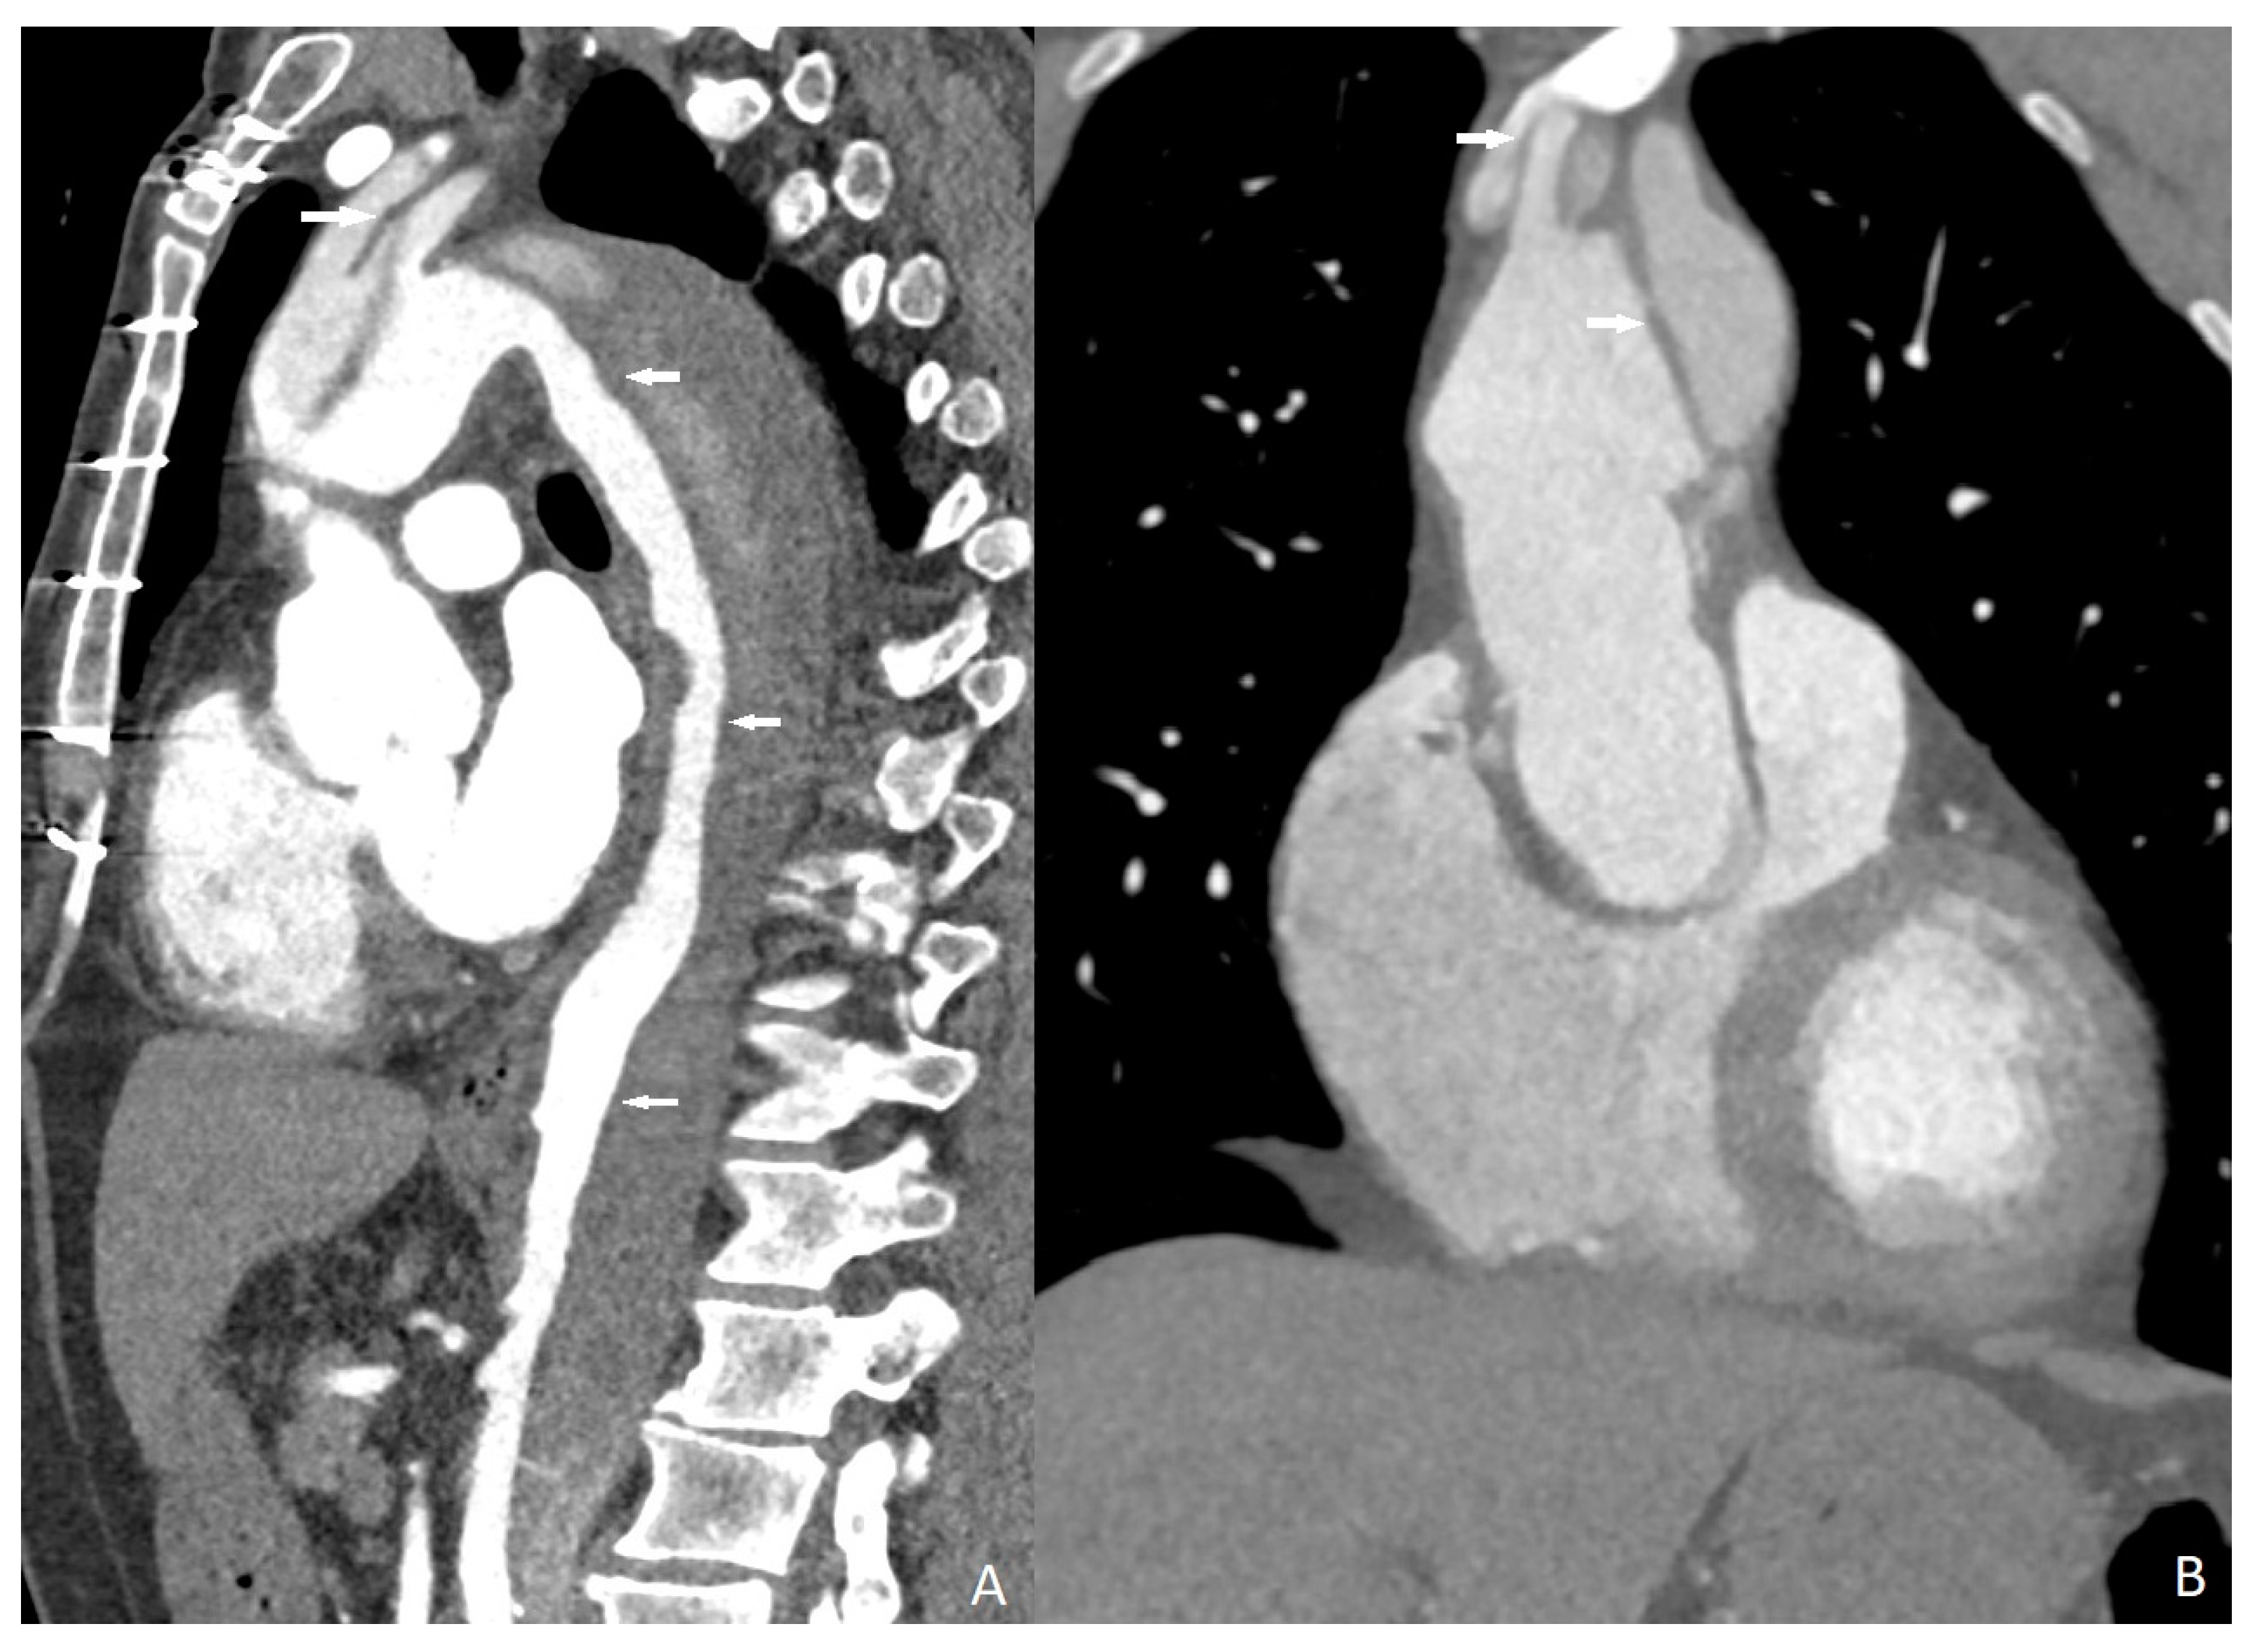

In 13 cases, myocardial perfusion deficits (PD) were identified (13/211, 18%). Cardiac magnetic resonance imaging and myocardial perfusion scintigraphy confirmed the presence of these myocardial PDs. Four of them were associated with substantial obstructive coronary artery disease. Myocardial perfusion abnormalities were observed to be associated with myocarditis in 9 individuals; however, finally, 13 patients were diagnosed with myocarditis (5 of them were identified with COVID-19-associated myocarditis, while the remaining 8 were diagnosed with nonspecific viral myocarditis). We could not define any myocardial PD in four of the myocarditis cases. Sensitivity, specificity, and positive and negative predictive values of quadruple-rule-out CT for myocarditis were 69.2% (95% confidence interval [CI] 65–74%), 100% (95%CI 96–100%), 100% (95%CI 96–100%), and 93.6% (95%CI 90–97%), respectively. Cohen’s coefficient of variation (ĸ value) for the presence of myocardial PD was 0.73 (substantial).

Perfusion deficits were found on DECT iodine map images with a subendocardial (n = 4, 30.7%), subepicardial (n = 7, 53.8%), and transmural (n = 2, 15.3%) anatomical location within the left ventricular wall (Figure 3). Subendocardial involvements were found in the patients who had obstructive CAD, and PDs correspond to associated coronary artery territories. Subepicardial and transmural PDs did not correspond to any coronary artery territories. ROI was used to measure the perfusion deficit and normal areas on the iodine map images on DECT. The mean value of the perfusion deficit areas was 162.13 ± 21.31 HU (range, 45–294), while that of the normal areas was 50.11 ± 9.32 HU (range, 23–91).

Figure 3.

Myocardial perfusion maps. Normal (A) perfusion image, subendocardial ((B), circle), transmural ((C), circle), and subepicardial ((D), arrows) perfusion deficits.